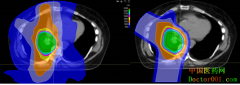

• 质子治疗精准靶向肿瘤 肺癌患者要好好考虑一下

日期:2018-10-16 11:30:12 点击:107 好评:0

根据2018年全球癌症流行病学报告,肺癌位居癌症发病率和死亡率第一名。肺癌有手术、化疗、靶向治疗、免疫治疗、放疗等多种治疗方法可供选择。手术往往无法清除所有存在的癌症,仅对早期癌症效果更佳,单靠化疗还不足以杀死100%的癌细胞,即使靶向药与免疫药...